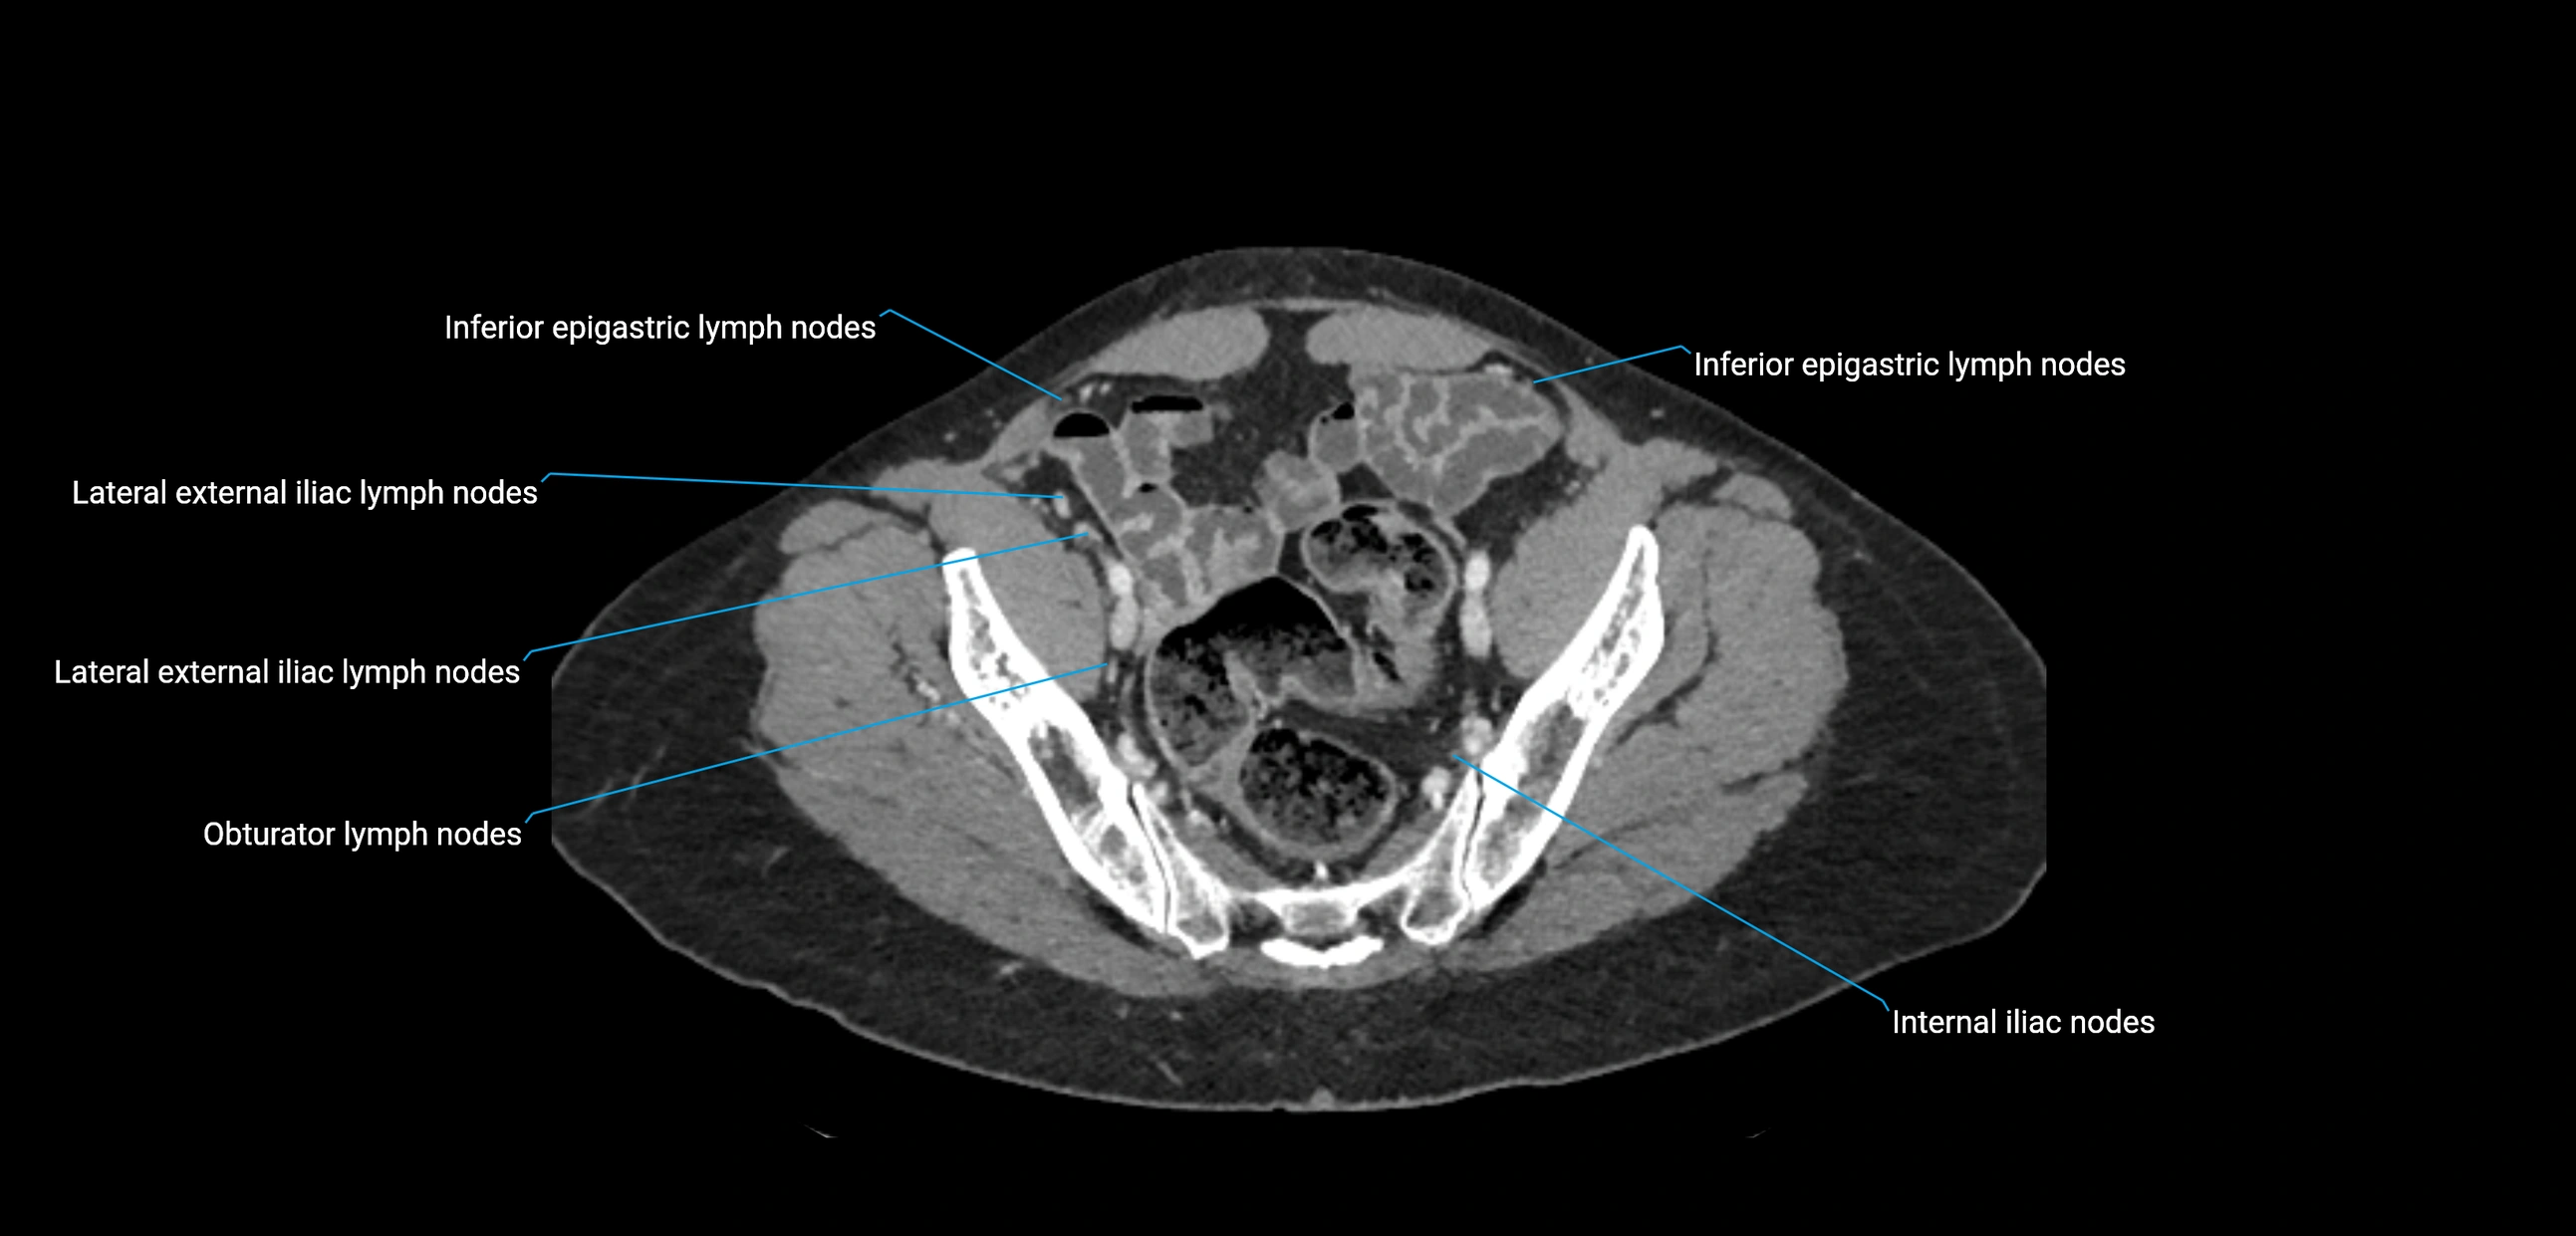

These nodes receive lymph from a wide range of abdominal and pelvic structures. Specifically, they drain lymph from the kidneys, suprarenal glands, gonads (testes/ovaries), uterus, uterine tubes, and pelvic organs, before converging into the lumbar lymphatic trunks, which terminate in the cisterna chyli → thoracic duct.

Clinically, the lateral aortic lymph nodes are critically important in oncology, being involved in the spread of testicular cancer, ovarian cancer, endometrial cancer, cervical cancer, renal malignancies, and retroperitoneal lymphomas. They are also key targets in retroperitoneal lymph node dissection (RPLND) for testicular tumors.

CT Appearance

CT Post-Contrast:

• Normal nodes enhance homogeneously

• Malignant nodes may show heterogeneous enhancement, central necrosis, or conglomerate formation

• Size >1 cm short axis is suspicious, though morphology and distribution are equally important

CT Venography (CTV):

• Demonstrates nodal encasement or compression of adjacent vessels (aorta, IVC, renal veins)

• Useful in staging testicular and ovarian malignancies

• Provides 3D reconstructions for retroperitoneal lymph node dissection planning